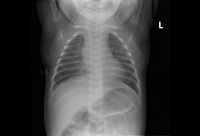

Respiratory syncytial virus infection

Atelectasis

From the personal collections of Melvin L. Wright, DO and Giovanni Piedimonte, MD; used with permission